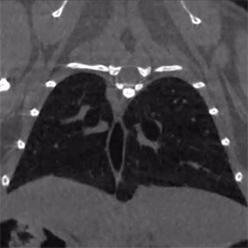

null Mediso nanoScan PET/CT

| Le sous-système CT du scanneur PET/CT permet de générer des images 3D à haute résolution par rayons X. |